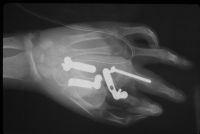

Clinical Examples: Trauma: Reconstruction of Dorsal Metacarpus with Latissimus Free Flap, Iliac Bone Graft and Tendon Grafts

This type of injury in a young woman resulted from a rollover car accident.

Progression of Xrays: injury; debridement; bone graft; after hardware removal: